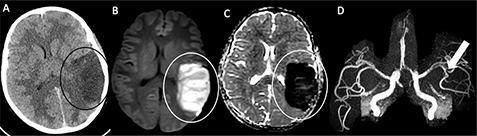

MRI, MR arteriography (MRA), and MR venography (MRV), potentially with the addition of perfusion imaging, are preferred to obtain a definitive diagnosis of both ischemic and hemorrhagic lesions, as well as to identify underlying arteriopathy, thrombus, or arterial dissection in both neonates and older children (Figure 3). Because of limited scanner time and need for patient sedation, many centers have implemented rapid or abbreviated brain MRI protocols for stroke. The protocols typically include diffusion-weighted imaging (DWI) and apparent diffusion coefficient (ADC) maps to diagnose ischemic stroke as well as gradient echo (GRE) sequences or susceptibility-weighted imaging (SWI) to detect hemorrhage (67). Perfusion maps using arterial spin labeling (ASL) to assess for areas at risk can also be performed, if available, but are not extensively validated in pediatric stroke (68). Contrast-enhanced perfusion imaging using either dynamic bolus passage of gadolinium with rapid T2* weighting (i.e., dynamic susceptibility contrast, DSC) or T1 (dynamic contrast enhancement, DCE) are less often utilized in children; however, if intravenous contrast administration is already anticipated for remaining post-contrast brain imaging sequences, DSC can seamlessly be added with a nominal investment of time. Mural arteriography, or so-called vessel wall imaging (VWI), particularly with gadolinium enhancement has emerged for its sensitivity to disorders within the vessel wall, including in the setting of active inflammatory process, such as in FCA, as well as to assess for intracranial arterial dissection on pre-contrast imaging (69).

Fig 3

Figure 3. An 11-year-old previously healthy male who presented with left-sided headache, emesis and changing voice. Axial (A) and coronal (B) CT images of the head demonstrate a geographic region of hypoattenuation in the left superior cerebellar hemisphere with loss of grey-white differentiation (circle). C. Axial DWI from MRI the same day demonstrates corresponding reduced diffusion in the left superior cerebellar artery territory (circle). 2D Time-of-Flight MRA of the neck demonstrate irregularity of the right (D) and left (E) vertebral arteries at the junction of the V2 and V3 segments (arrows). Axial CT angiogram (F) confirms irregularity in the vertebral arteries, compatible with bilateral vertebral artery dissection (arrows).

Catheter angiography can be considered when the cause of the infarction is unclear from clinical or laboratory features, or non-invasive imaging studies, and when high clinical suspicion of an arteriopathy remains, due to its sensitivity for vasculopathy in medium and small vessels, shunt physiology, aneurysms, or other structural vascular disorders (70). Perfusion imaging is particularly important in the setting of vasculopathy such as moyamoya disease, when revascularization procedures such as bypass or synangiosis are considered, to assess hemodynamic changes before and after revascularization (71). We hasten to add that the use of commonly cited perfusion parameters in adult AIS, whether from DSC or CT perfusion, in the management of childhood AIS remains unestablished and considerable baseline anatomic, physiologic, and hemodynamic differences are to be anticipated.